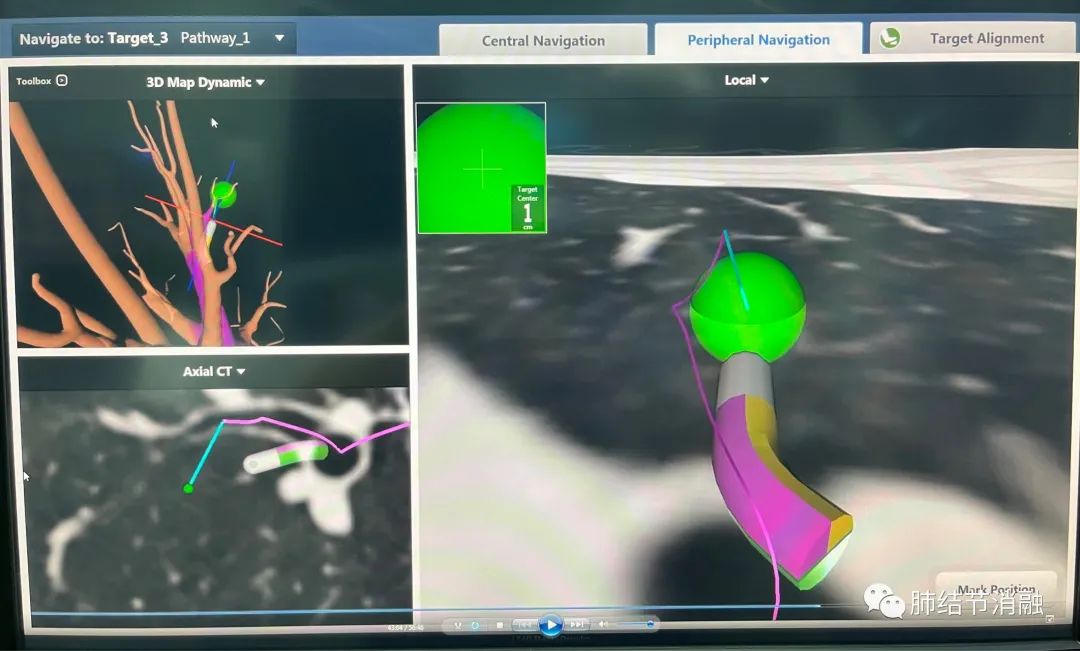

磁导航定位主病灶

磁导航定位次要病灶1

磁导航定位次要病灶2,这个病灶难度最大,就在气管边上,需要打隧道才能达到,我们在接近结节附近染色。

电磁导航设备相当于支气管镜检查操作中的“北斗”导航,其优势在于采用类似“GPS”的定位系统,在超细导管配合下,探头可以根据事先的设定路径,精准地找到结节。对于多发结节的治疗上优势明显,创伤小,并发症低。